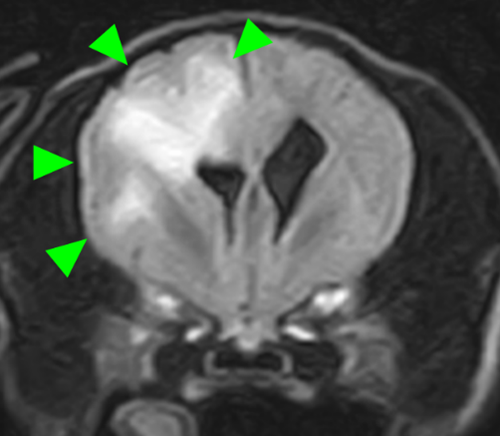

右前頭葉にT2 強調画像/FLAIR 画像で高信号、T1 強調画像で一部低信号を示し、辺縁部で一部造影増強を示すびまん性の所見を認めた。この所見は、DWI 画像で高信号、ADC-map で大半が等~低信号を示していた。また左側前頭葉にも同様の信号所見を示す微小病変を認めた。

T2強調画像 横断像

FLAIR画像 横断像